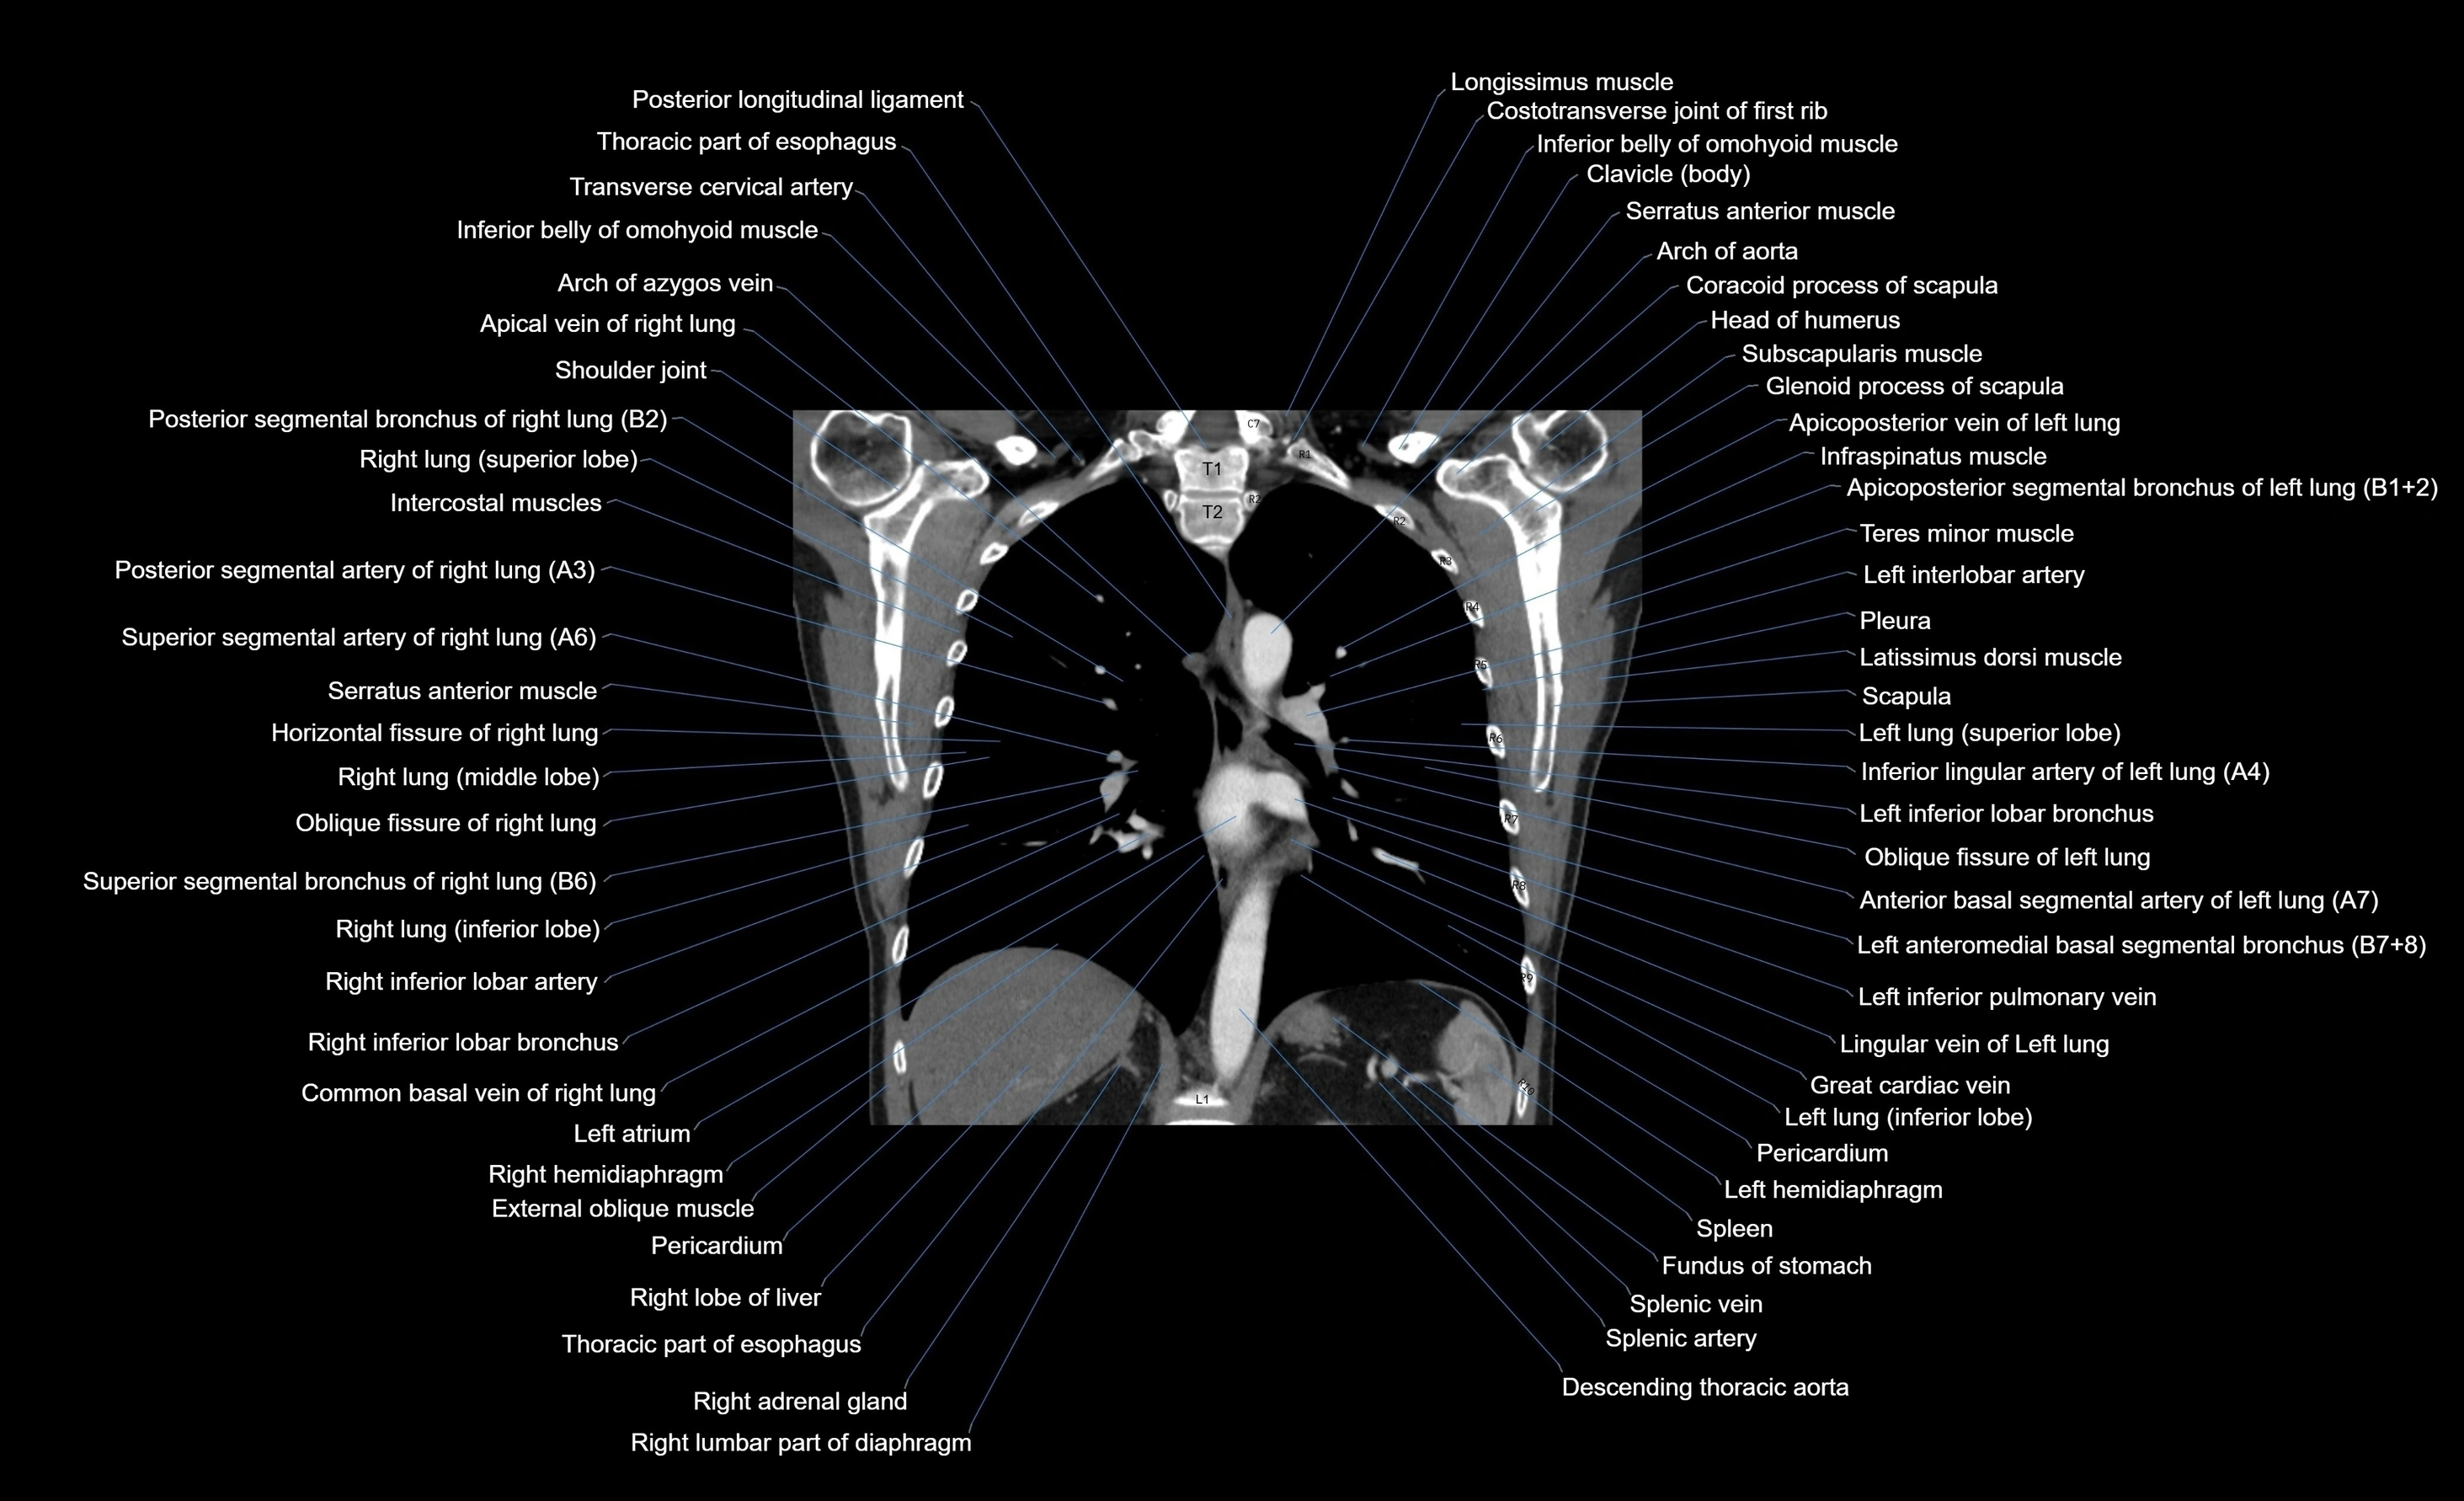

CT images